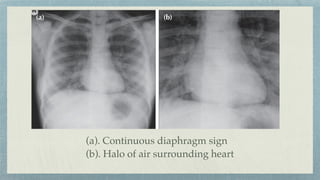

(a). Continuous diaphragm sign

(b). Halo of air surrounding heart

(c). Pneumopericardium

(a). Pneumothorax (b). Pneumomediastinum